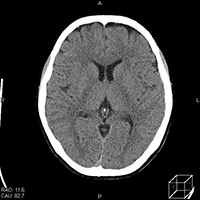

CT画像(例)

頭部